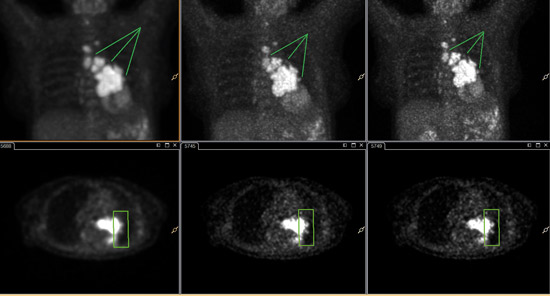

Mit ×Fine für diesen Lungenkrebspatienten rekonstruierte Bilder zeigen eine verbesserte Erkennbarkeit von Läsionen.

Bilder mit freundlicher Genehmigung des Universitätsklinikums Salzburg, Österreich

×Fine und ×Sharp steigern die Bildqualität, hier in verbesserter Auflösung. ×Fine-Rekonstruktion (Mitte) und ×Fine-Rekonstruktion mit ×Sharp (rechts).